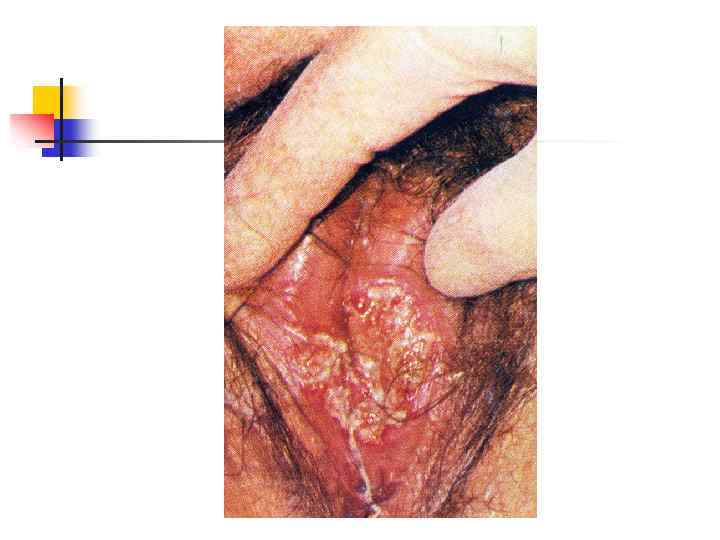

Герпес половых органов: рецидив На больших половых губах и коже бёдер видны беспорядочно расположенные эрозии. Окружающие ткани гиперемированы. Высыпания почти не беспокоят больную

Герпес половых органов: рецидив На больших половых губах и коже бёдер видны беспорядочно расположенные эрозии. Окружающие ткани гиперемированы. Высыпания почти не беспокоят больную